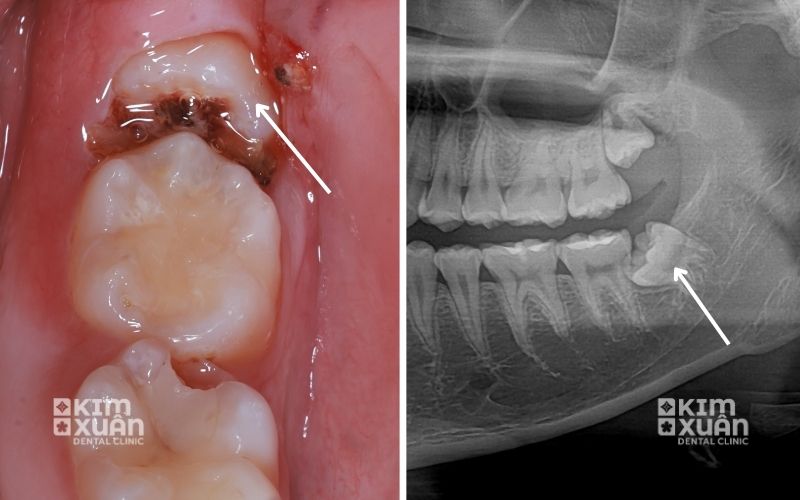

Bước 1: Thăm khám và chụp X-quang

Bác sĩ tiến hành thăm khám tổng quát, kết hợp chụp X-quang để đánh giá chính xác vị trí răng sâu, hình dạng - số lượng chân răng và mức độ viêm nhiễm. Đây là bước quan trọng giúp bác sĩ lựa chọn phương pháp nhổ răng phù hợp, hạn chế rủi ro trong quá trình thực hiện.